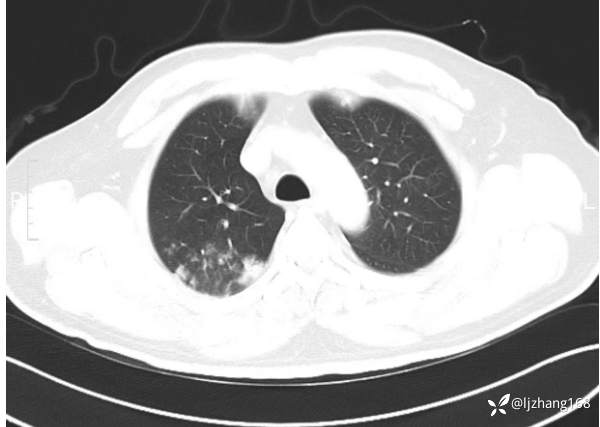

中年男患,右肺团片影,炎症0R肿瘤?

患者年龄:47岁

主诉:咳嗽、 咳痰伴气短20+天

简要病史: 20+天前患者因受凉后出现阵发性咳嗽,咳少量白色粘痰,痰易咳出,伴活动后气短,伴纳差、乏力、全身酸痛,伴多汗,无痰中带血及咯血,无发热、畏寒及寒战,无潮热、盗汗,无夜间阵发性呼吸困难及端坐呼吸,无声嘶,无头晕、头痛,无黑矇、晕厥及意识障碍,无腹痛、呕血及黑便等不适,遂就诊于当地医院予以输液等治疗后未见明显好转(具体诊疗不详),现为进一步诊治就诊于我院门诊,以“右肺占位”收入我科。病来饮食欠佳,近期体重下降(具体不详)。既往糖尿病病史7+年,未规律监测血糖,血糖控制不佳。否认“高血压、冠心病及慢性肾脏病”等慢性疾病史。否认“肝炎、结核、伤寒”等传染病史。否认食物、药物过敏史。否认外伤、输血史,预防接种史不详。

辅助检查:糖化血红蛋白12.3%。肺炎支原体IgG、IgM、呼吸道合胞病毒均未见明显异常。胸部CT:右肺上叶阻塞性肺炎。